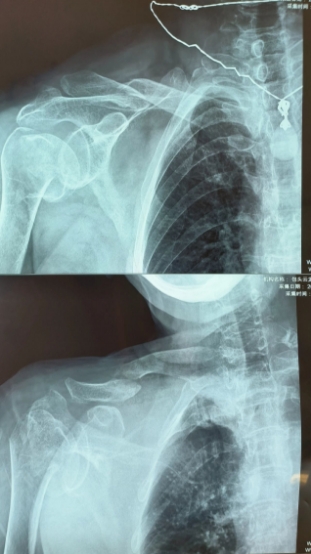

72岁的患者张女士没有想到,一次意外摔倒竟导致自己身体多处损伤。“右肱骨近端粉碎性骨折、右锁骨骨折、右冈上肌、斜方肌、右肩胛下肌肌腱损伤、右肩关节积液、右胫骨平台骨折、右腓骨头骨折、右膝关节积液、右侧第二肋骨骨折、多处软组织损伤、骨质疏松症”,患者病情复杂且严重。面对这样的挑战,创伤科李培龙团队经过深思熟虑,为患者提供了详细的诊疗方案。经与患者家属反复沟通,患者对生活质量要求较高,且患者损伤类型符合反肩关节置换手术的指征,决定采用这一先进的手术技术进行治疗。

反肩关节置换术(Reverse Total Shoulder Arthroplasty, RTSA)是一种复杂而精细的手术,其主要目的是在肩部损伤严重的老年病人或肩袖严重撕裂无法修复的情况下,通过反向安装人工肩关节来恢复患者的肩关节功能。与传统的肩关节置换手术不同,反肩关节置换术将人工肱骨头置于肩胛盂上,而肩胛盂假体则固定于肱骨近端,从而实现肩关节旋转中心的内移和下移,进而增大三角肌的力臂,形成稳定的力学支点。